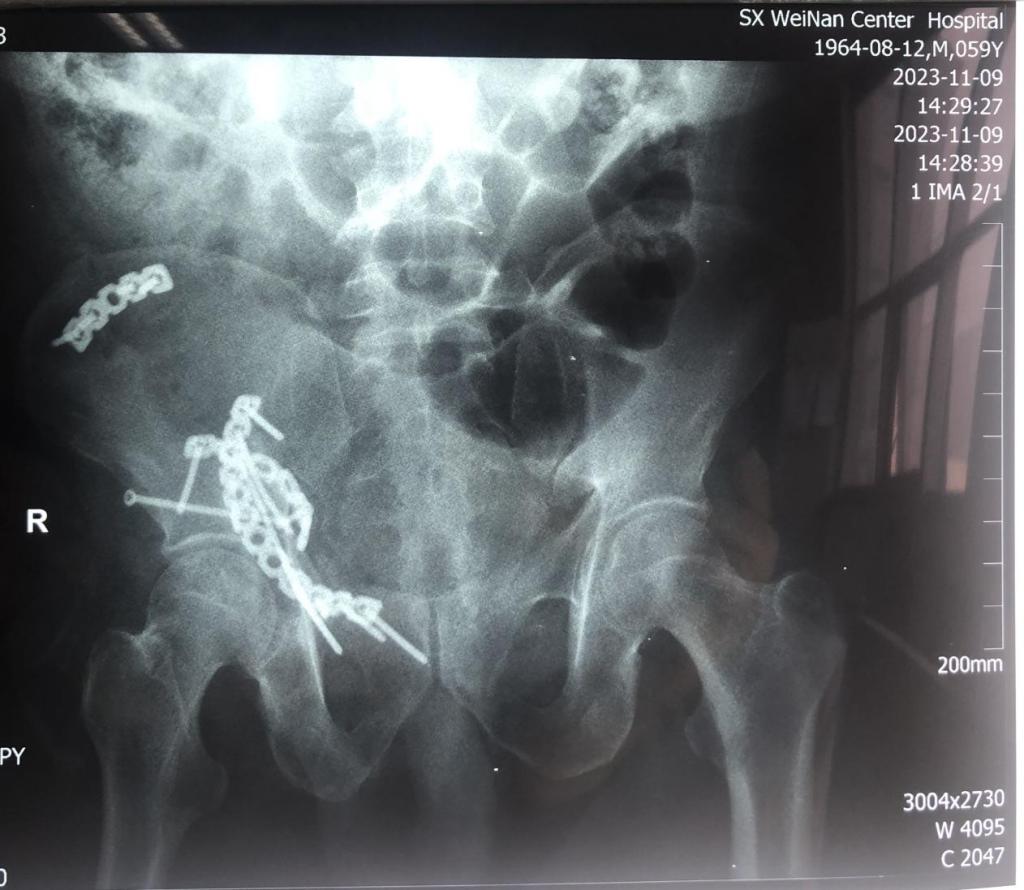

经严谨的术前规划及方案设计,11月7号由郭宏军主任医师医疗组给予单一前方经腹直肌旁入路手术内固定。术后患者右髋关节功能恢复良好,自行翻身,半靠体位均不受限。

复杂髋臼骨折是创伤骨科皇冠上的明珠,手术难度大,风险高、技术要求高,采用单一腹直肌旁入路手术治疗是目前国内外的主流趋势,相较于髂腹股沟入路有明显的微创效果,显露骨折面充分广泛,固定方便可靠。

该患者伤后三周手术,骨折端已明显骨痂包绕,显露不易,术后给予高位前柱截骨使得髋臼骨折易于解剖复位固定,恢复了髋臼关节面光滑连续完整,头臼匹配良好,预防了股骨头后期坏死,使患者能够早期功能锻炼,最大程度减少了致残率,早日恢复劳动力。